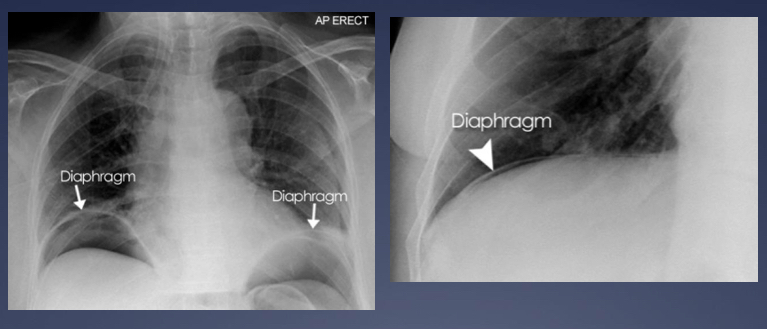

What is this abdominal x-ray showing?

What is being shown on this abdominal x-ray?

Label the viscera on the abdominal x-ray.